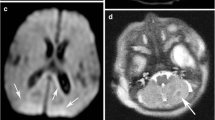

Perinatal brain lesions are at their most visually obvious between 1 and 2 weeks from delivery (Fig. 5). This is convenient as neonates may be clinically stable and off assisted ventilation by this time. Neonatologists may request earlier scanning in order to make a diagnosis or to assist in clinical management. Imaging within the first couple of days may show only subtle abnormalities in the presence of significant brain injury. Early image examinations should always include DWI. DWI should identify any infarcted WM (Fig. 2), but is not always so reliable at detecting significant injury to the basal ganglia and thalami (Fig. 6). As for adult stroke, the DWI visual appearances of infarcted tissue are obvious very early and last for approximately 1 week, by which time conventional imaging should be obviously abnormal [6, 7]. Sometimes visual analysis of the DWI is unremarkable or difficult to interpret (Fig. 7), even in the presence of severe damage. Most scanners have the software necessary to obtain apparent diffusion coefficients (ADC) from the trace diffusion images. It is recommended that ADC values are measured in all infants even when the DWI appears normal (Fig. 7). During the first week from injury ADC values are usually decreased in the presence of ischaemic WM, but may be reduced, normal or elevated in clinically significant basal ganglia lesions. Difficulties in interpreting DWI findings have led to studies using diffusion tensor techniques to explore tissue microstructure further (see advanced techniques).

Left panel DWI in three orthogonal planes of sensitisation does not show any focal high-signal intensity with ADC values. The actual ADC values (×10−3 mm−2 s−1) in tissue with normal values in parentheses. b Follow-up imaging showing extensive infarction in both white and central grey matter. Measuring the ADC values will correctly identify ischaemic tissue when there is widespread abnormality

Most modern scanners have the ability to perform DWI. Images may be obtained very quickly and are probably best left to the end of the imaging examination as the noise may wake the sleeping infant. There are relatively few studies using DWI in infants with HIE and these have had conflicting results [11–14]. As for unilateral infarction DWI will usually normalize by the end of the first week, both visually and in terms of ADC values. In infants with HIE, ADC values are significantly reduced in the first week following severe injury to either the WM or BGT (P<0.0001), but values have normalized by the end of the first week and then increase during the second week. We have found that ADC values <1.1×10−3/mm2 are always associated with WM infarction and values <0.8×10−3/mm2 with thalamic infarction [5].

Early visual analysis may be particularly misleading when there has been widespread injury to the WM and BGT, probably because there is no normal tissue for comparison (Fig. 7). A visual clue may be found by observing the appearance of the usually normal-appearing cerebellum (Fig. 11). In these infants, measuring the ADC values will correctly detect the presence of ischaemic tissue. Worrying, however, is that both the early visual appearances of DWI and the ADC values may be normal in the presence of isolated but clinically significant BGT lesions. We have shown that ADC values are either normal or increased in moderate BGT and WM lesions when compared to controls [5]. Moderate WM abnormalities are associated with relatively good outcome: normal motor development, but higher risk of cognitive impairment. Moderate BGT lesions are usually associated with significant motor impairment in the form of quadriplegic cerebral palsy. It is, therefore, very important to be able to correctly detect both these types of moderate lesions. More sophisticated diffusion techniques may improve our ability to identify moderate abnormalities.